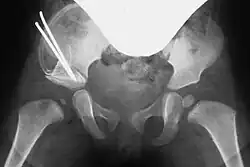

Preoperative planning involves conventional pelvic X-rays, including pelvic overview and Rippstein view images, to assess joint misalignment, severity, and surgical planning. Rippstein views provide a lateral projection of the femoral necks.[7][8]

In cases of dysplastic hip dislocation, a functional arthrography of the hip joint(s) may be performed first to assess dislocation behavior and the extent of capsular stretching or injury on X-ray. This step helps determine whether surgery is necessary and which technique to use.[7]

Acetabuloplasty, Step 4: Optional fixation with a Kirschner wire